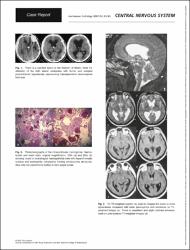

Intraventricular meningiomas have often been reported; however, literature reveals very few cases localized within foramen of Monro. Herein we report a 57-year-old woman admitted with obstructive hydrocephalus-related symptoms. Strikingly, the lesion was completely calcified in CT and had no marked solid component on MRI. The lesion was completely removed by surgical resection with a transfrontal intraventricular approach. The resected mass was histopathologically diagnosed as meningioma. The patient's symptoms resolved immediately after the operation.

Calcification, Foramen of Monro, Intraventricular, Mass, Meningioma, Diagnosis, Radiology, Nuclear medicine & medical imaging